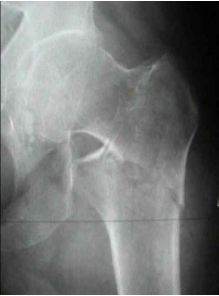

53 下圖為 60 歲男性走路自跌,左髖疼痛。下列敘述何者正確? (A)為不穩定骨折 (B)是順轉子間型骨折 (C)易發生股骨頭缺血性壞死 (D)此為囊內骨折